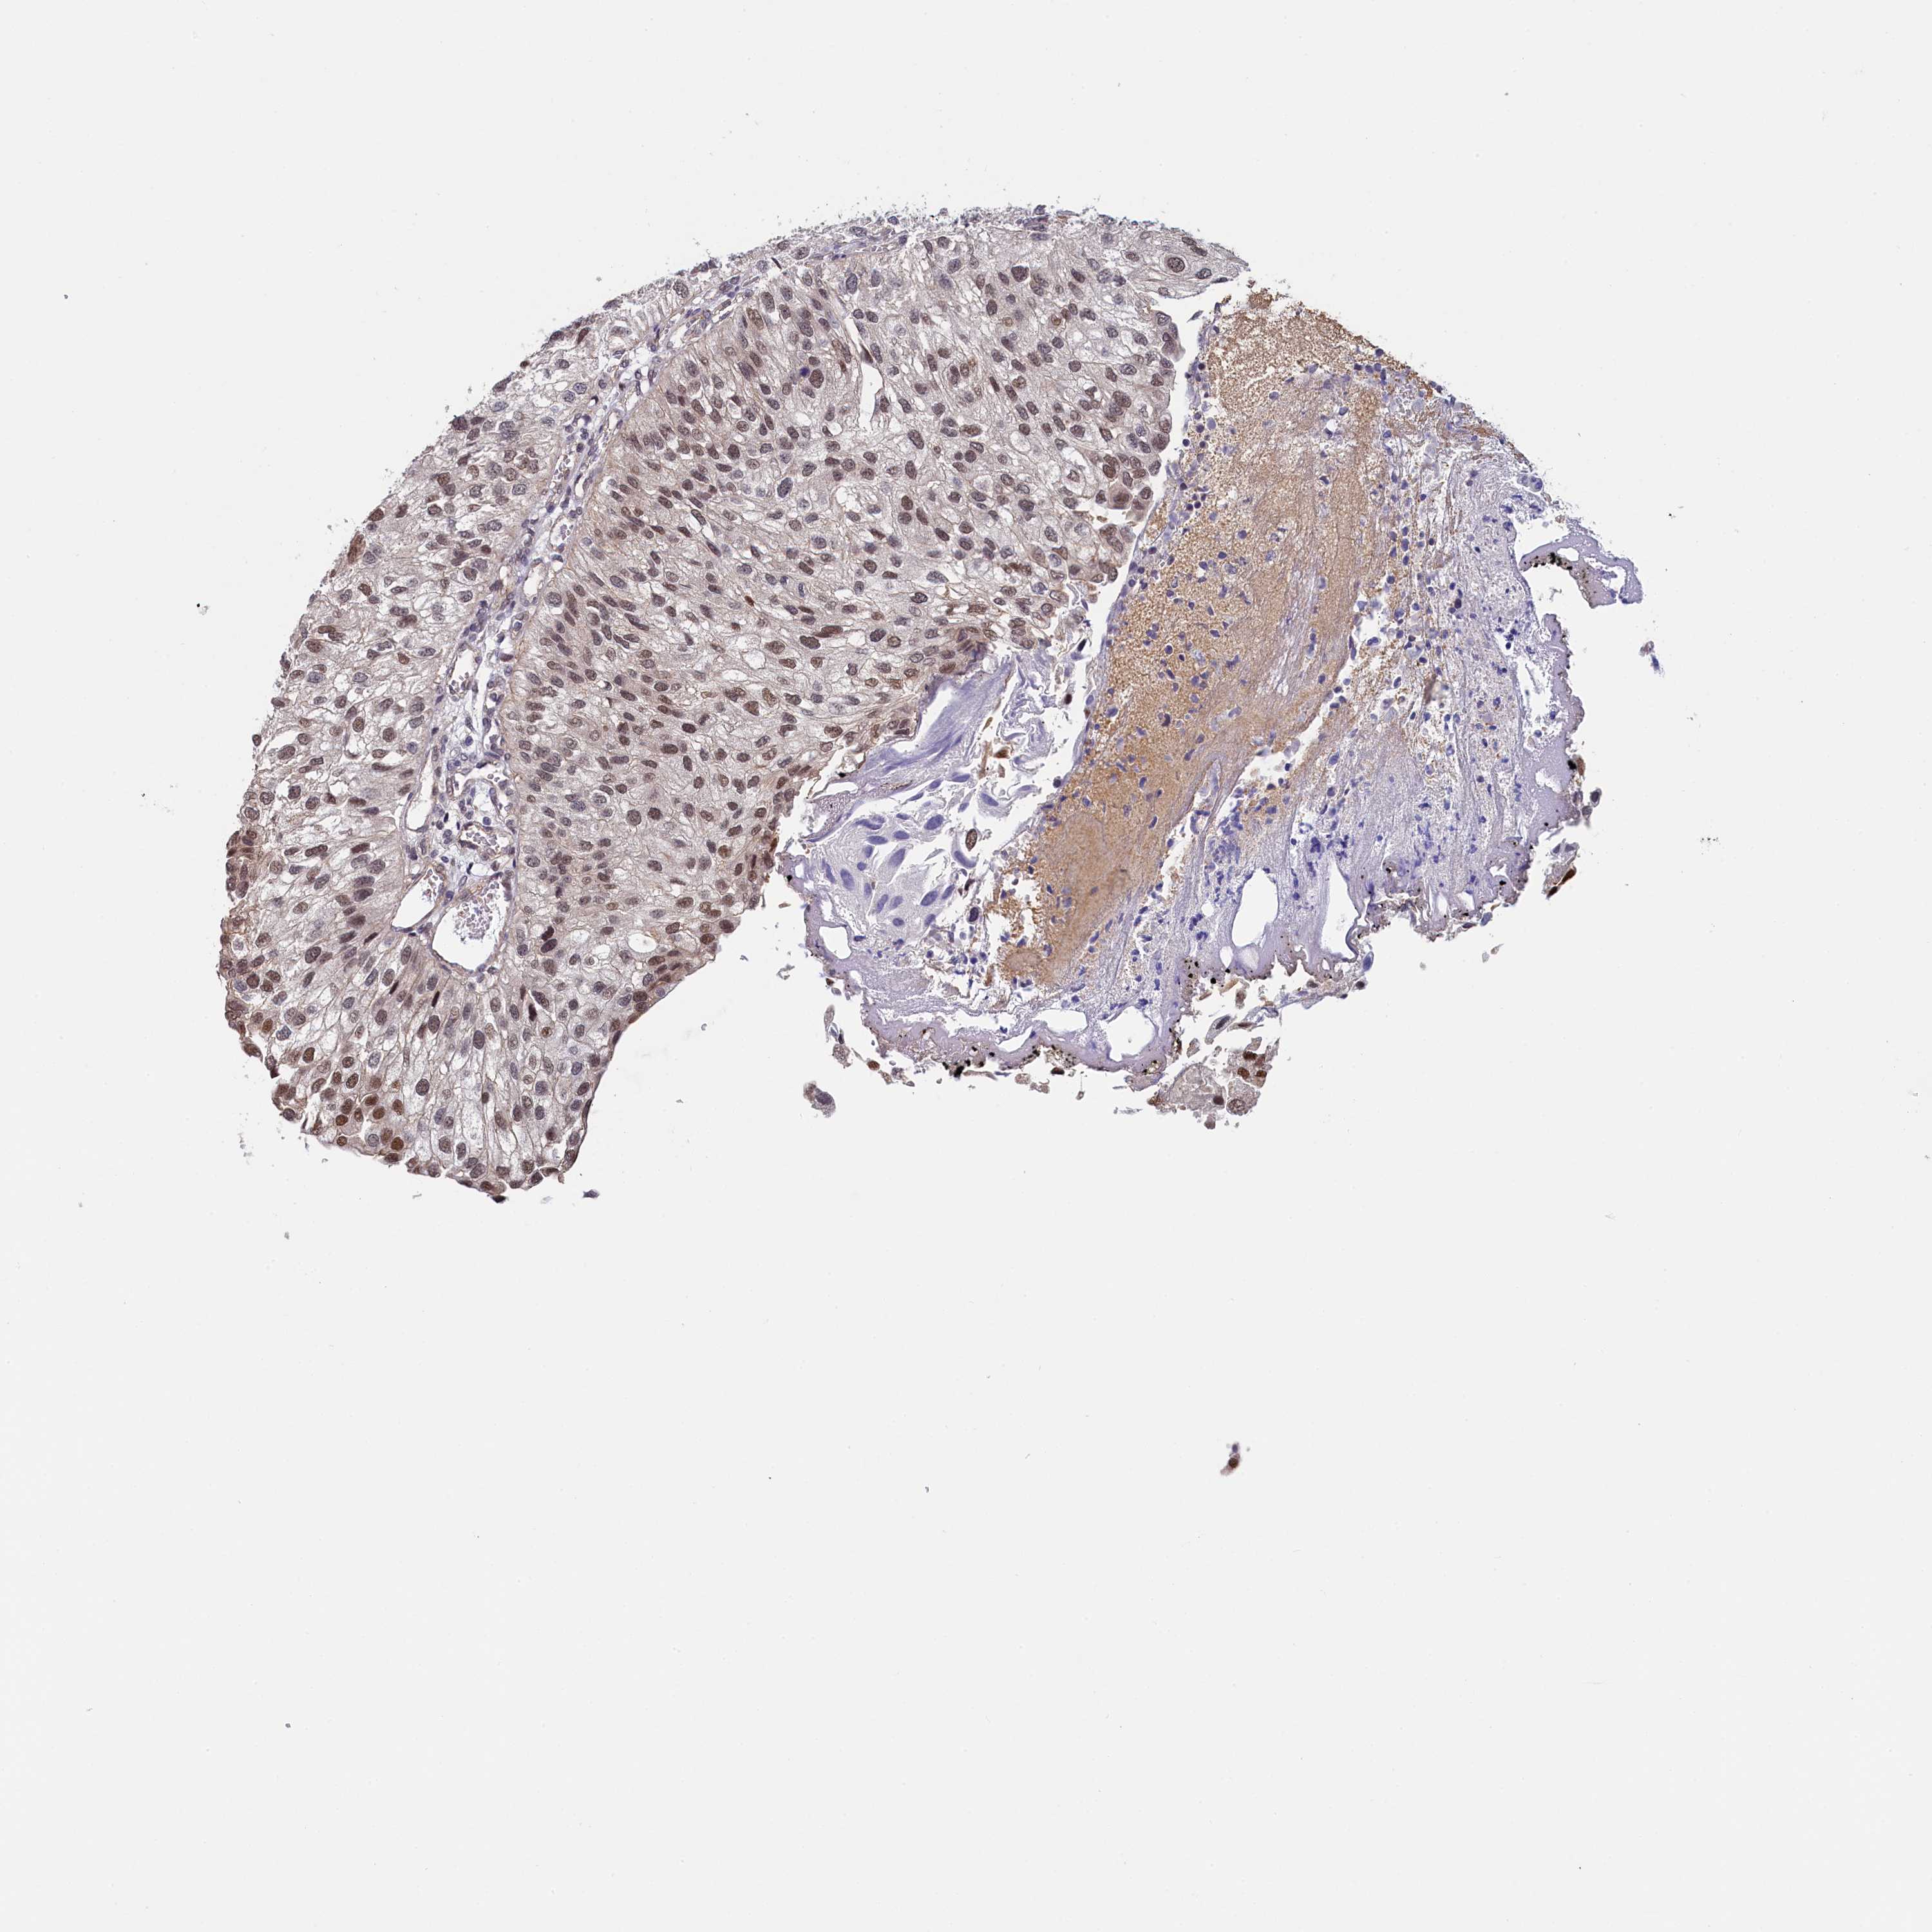

UROTHELIAL CANCER - Protein expressioni

A mouse-over function shows sample information and annotation data. Click on an image to view it in a full screen mode. Samples can be filtered based on level of antibody staining by selecting one or several of the following categories: high, medium, low and not detected. The assay and annotation is described here.

Note that samples used for immunohistochemistry by the Human Protein Atlas do not correspond to samples in the TCGA dataset.

Antibody stainingi

Antibody staining in the annotated cell types in the current human tissue is reported as not detected, low, medium, or high, based on conventional immunohistochemistry profiling in selected tissues. This score is based on the combination of the staining intensity and fraction of stained cells.

Each image is clickable and will lead to virtual microscopy that enables deeper exploration of all samples and also displays staining intensity scores, fraction scores and subcellular localization as well as patient and tissue information for each sample.

Antibody HPA040255

Antibody HPA040651

Staining

High

Medium

Low

Not detected

Intensity

Strong

Moderate

Weak

Negative

Quantity

>75%

75%-25%

<25%

None

Location

Nuclear

Cytoplasmic/membranous

Cytoplasmic/membranous,nuclear

Urothelial carcinoma, High grade

Urothelial carcinoma, Low grade